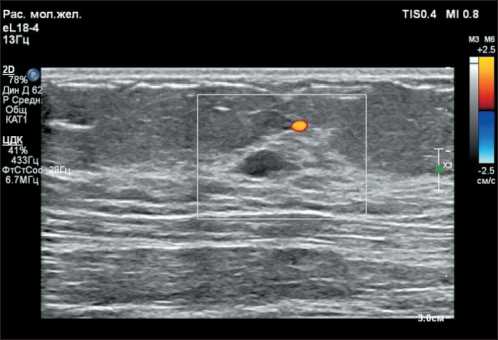

При УЗИ молочных желез через 4 мес после первичного обследования: BI-RADS-4а справа, BI-RADS-2 слева. Эхо-картина фиброзно-кистозных изменений молочных желез с преобладанием железистой ткани. В правой молочной железе на 12 часах условного циферблата определяется гипоэхогенное образование овальной формы с четким ровным контуром, размерами 1,0×0,4 см, периферическим кровотоком, предположительно фиброаденома, отмечен некоторый рост в динамике от марта 2024 г., выполнена трепан-биопсия. Аксиллярные лимфатические узлы с сохраненной дифференцировкой (рис. 1, 2).

Рис. 1. УЗ-картина гипоэхогенного образования на границе верхних квадрантов правой молочной железы.

Примечание: рисунок выполнен авторами

Fig. 1. Ultrasound image of hypoechoic lesion at the border of the upper quadrants of the right breast. Note: created by the authors

Рис. 2. Допплеровское картирование: демонстрация периферического кровотока.

Fig. 2. Doppler mapping: demonstration of peripheral blood flow. Note: created by the authors